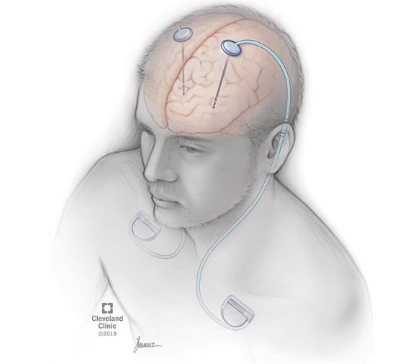

Deep Brain Stimulation (DBS)

Since OCD has been associated with hyperactivity of the cortico-striato-thalamocortical (CSTC) network, electrical stimulation is assumed to be effective as it induces a resetting of network oscillatory patterns across the CSTC network. Overall, DBS in OCD may decrease 40–60% of symptoms in at least half of patients. DBS has the potential to become the preferential treatment for a specific group of seriously ill, therapy-refractory OCD patients due to the low risk of the operation, the reversible nature of the technique, and the possibility to optimize treatment postoperatively (Zohar, 2012, p.94).

Figure 3. DBS (cleavelandclinc.org)